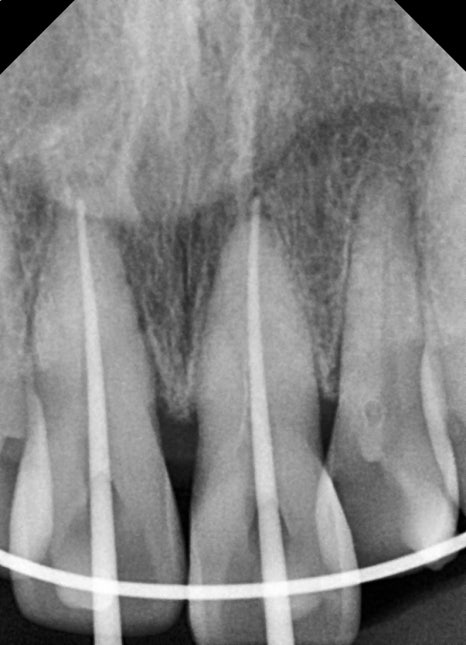

After the recovery period, root canal treatment for the front teeth

Teeth that have received a strong impact

may develop sensitivity, pain, or discoloration weeks to months later.

This is due to nerve damage.

For this patient as well, the possibility of nerve necrosis in the two front teeth was confirmed,

and after accurate working length measurement,

root canal treatment was performed.

If root canal treatment is not performed correctly, apical periodontitis or retreatment may be needed later,

so in front tooth trauma, it is safer to treat at the proper time rather than “just watch and wait.”